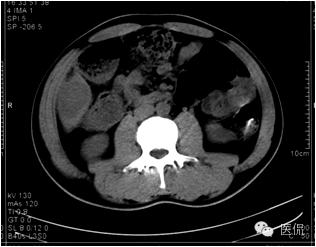

门脉期上述部位持续强化,程度加重,且环壁影增厚,核心样结节、分隔明显。